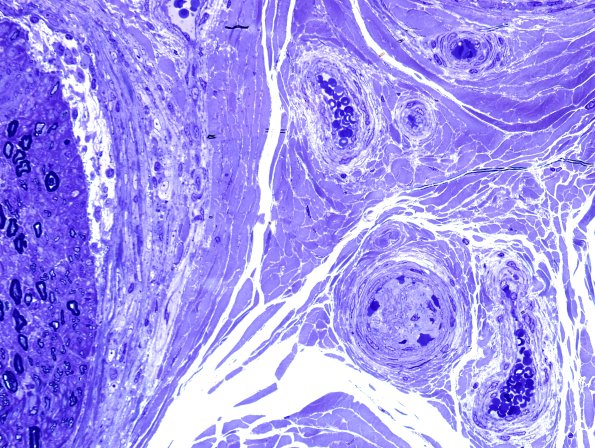

Washington University Experience | PERIPHERAL NEUROPATHY | 11 VASCULITIS - VASCULOPATHY | 2 Vasculopathy | 2C2-Perineuritis-Vasculopathy-Case-2-Plastic-1.jpg

2C2,3 An apparently occluded/thrombosed blood vessel with no evidence of inflammation/necrosis. (plastic sections)